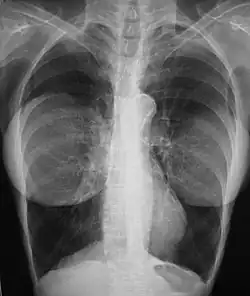

![]() The pre-operative aspects (left), and the post-operative aspects (right) of a bilateral, sub-muscular emplacement of 350 cc saline implants through an infra-mammary fold (IMF) incision | |